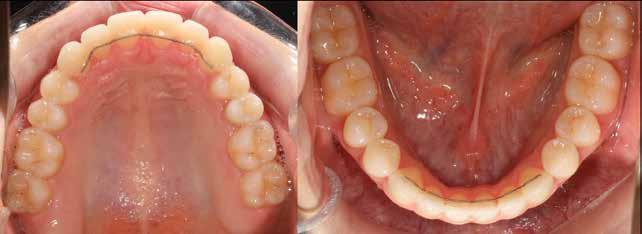

Lány páciensem I. fázisú kezelését 10 évesen kezdtük el bimaxilláris funkciós, kivehető készülékkel. Megfigyelhetőek a class 2-es eltérésnél tipikusan jellemző szűk felső és alsó fo-

gívek, valamint a nagy overjet, a mandibula disztál helyzete, továbbá a felső metszőfogak protrúziója, amelynek kialakulásához sokszor hozzájárul az ujjszopás is (1-3. képek)

A vegyes fogazati kezelési célok a fogívek tágítása és a mandibula meziális irányú növekedésének a biztosítása volt. Fontos, hogy az ilyen típusú készülékeket nem csak éjszaka, hanem napközben is – amennyit csak lehet – hordani kell a minél hatékonyabb működés érdekében. A 18 hónapos első fázisú kezelésnek köszönhetően az alap kezelési célok megvalósultak, sikerült a class 1-es okklúziót beállítani (4-7. képek).